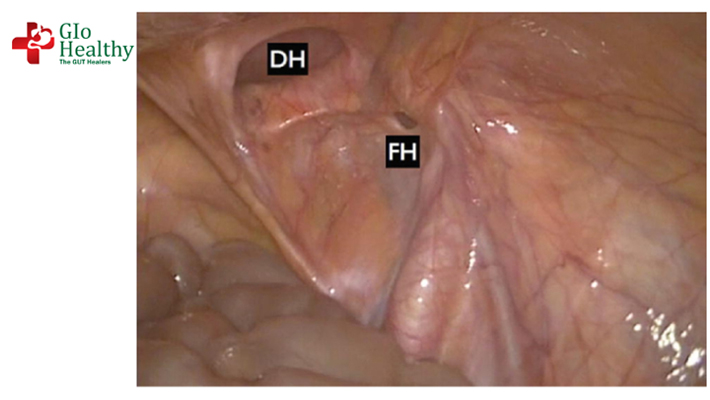

A Femoral Hernia is an uncommon type of Hernia. Femoral Hernias sometimes appear as a painful lump in the inner upper part of the thigh or groin. The lump can often be pushed back in or disappears when you lie down. Coughing or straining may make the lump appear.